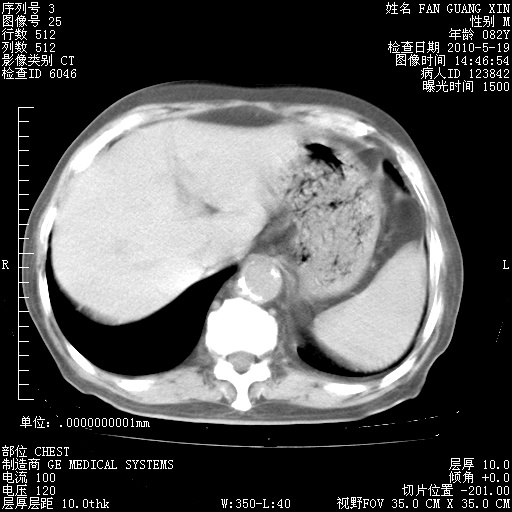

再治疗10天后的肺部CT

阅读此次胸部CT,肺间质渗出性改变较入院时有吸收。目前从体温、白细胞、中性分叶明显增高,肯定存在细菌感染(发生医院感染哦,若无消化道及泌尿系统等感染的依据,肺部感染可能大)。若你院头孢哌酮舒巴坦钠耐药率较高,同意你的方案,若48小时体温仍高,可考虑使用碳青霉稀类抗菌药物,同时可予超声雾化、注意滴数时加大液体量。白蛋白33.30g/L较低哦,需加强营养等支持治疗。